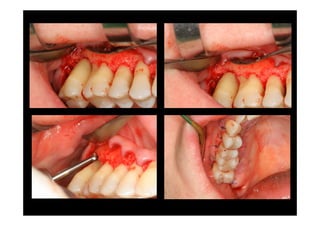

SUBGINGIVAL

CURETTAGE

BEFORE AND

FOUR WEEKS

AFTER

PROCEDURE